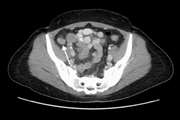

Ultrasound and magnetic resonance imaging features of fetal urogenital anomalies: A pictorial essay Jul 15 2025 - 10:59